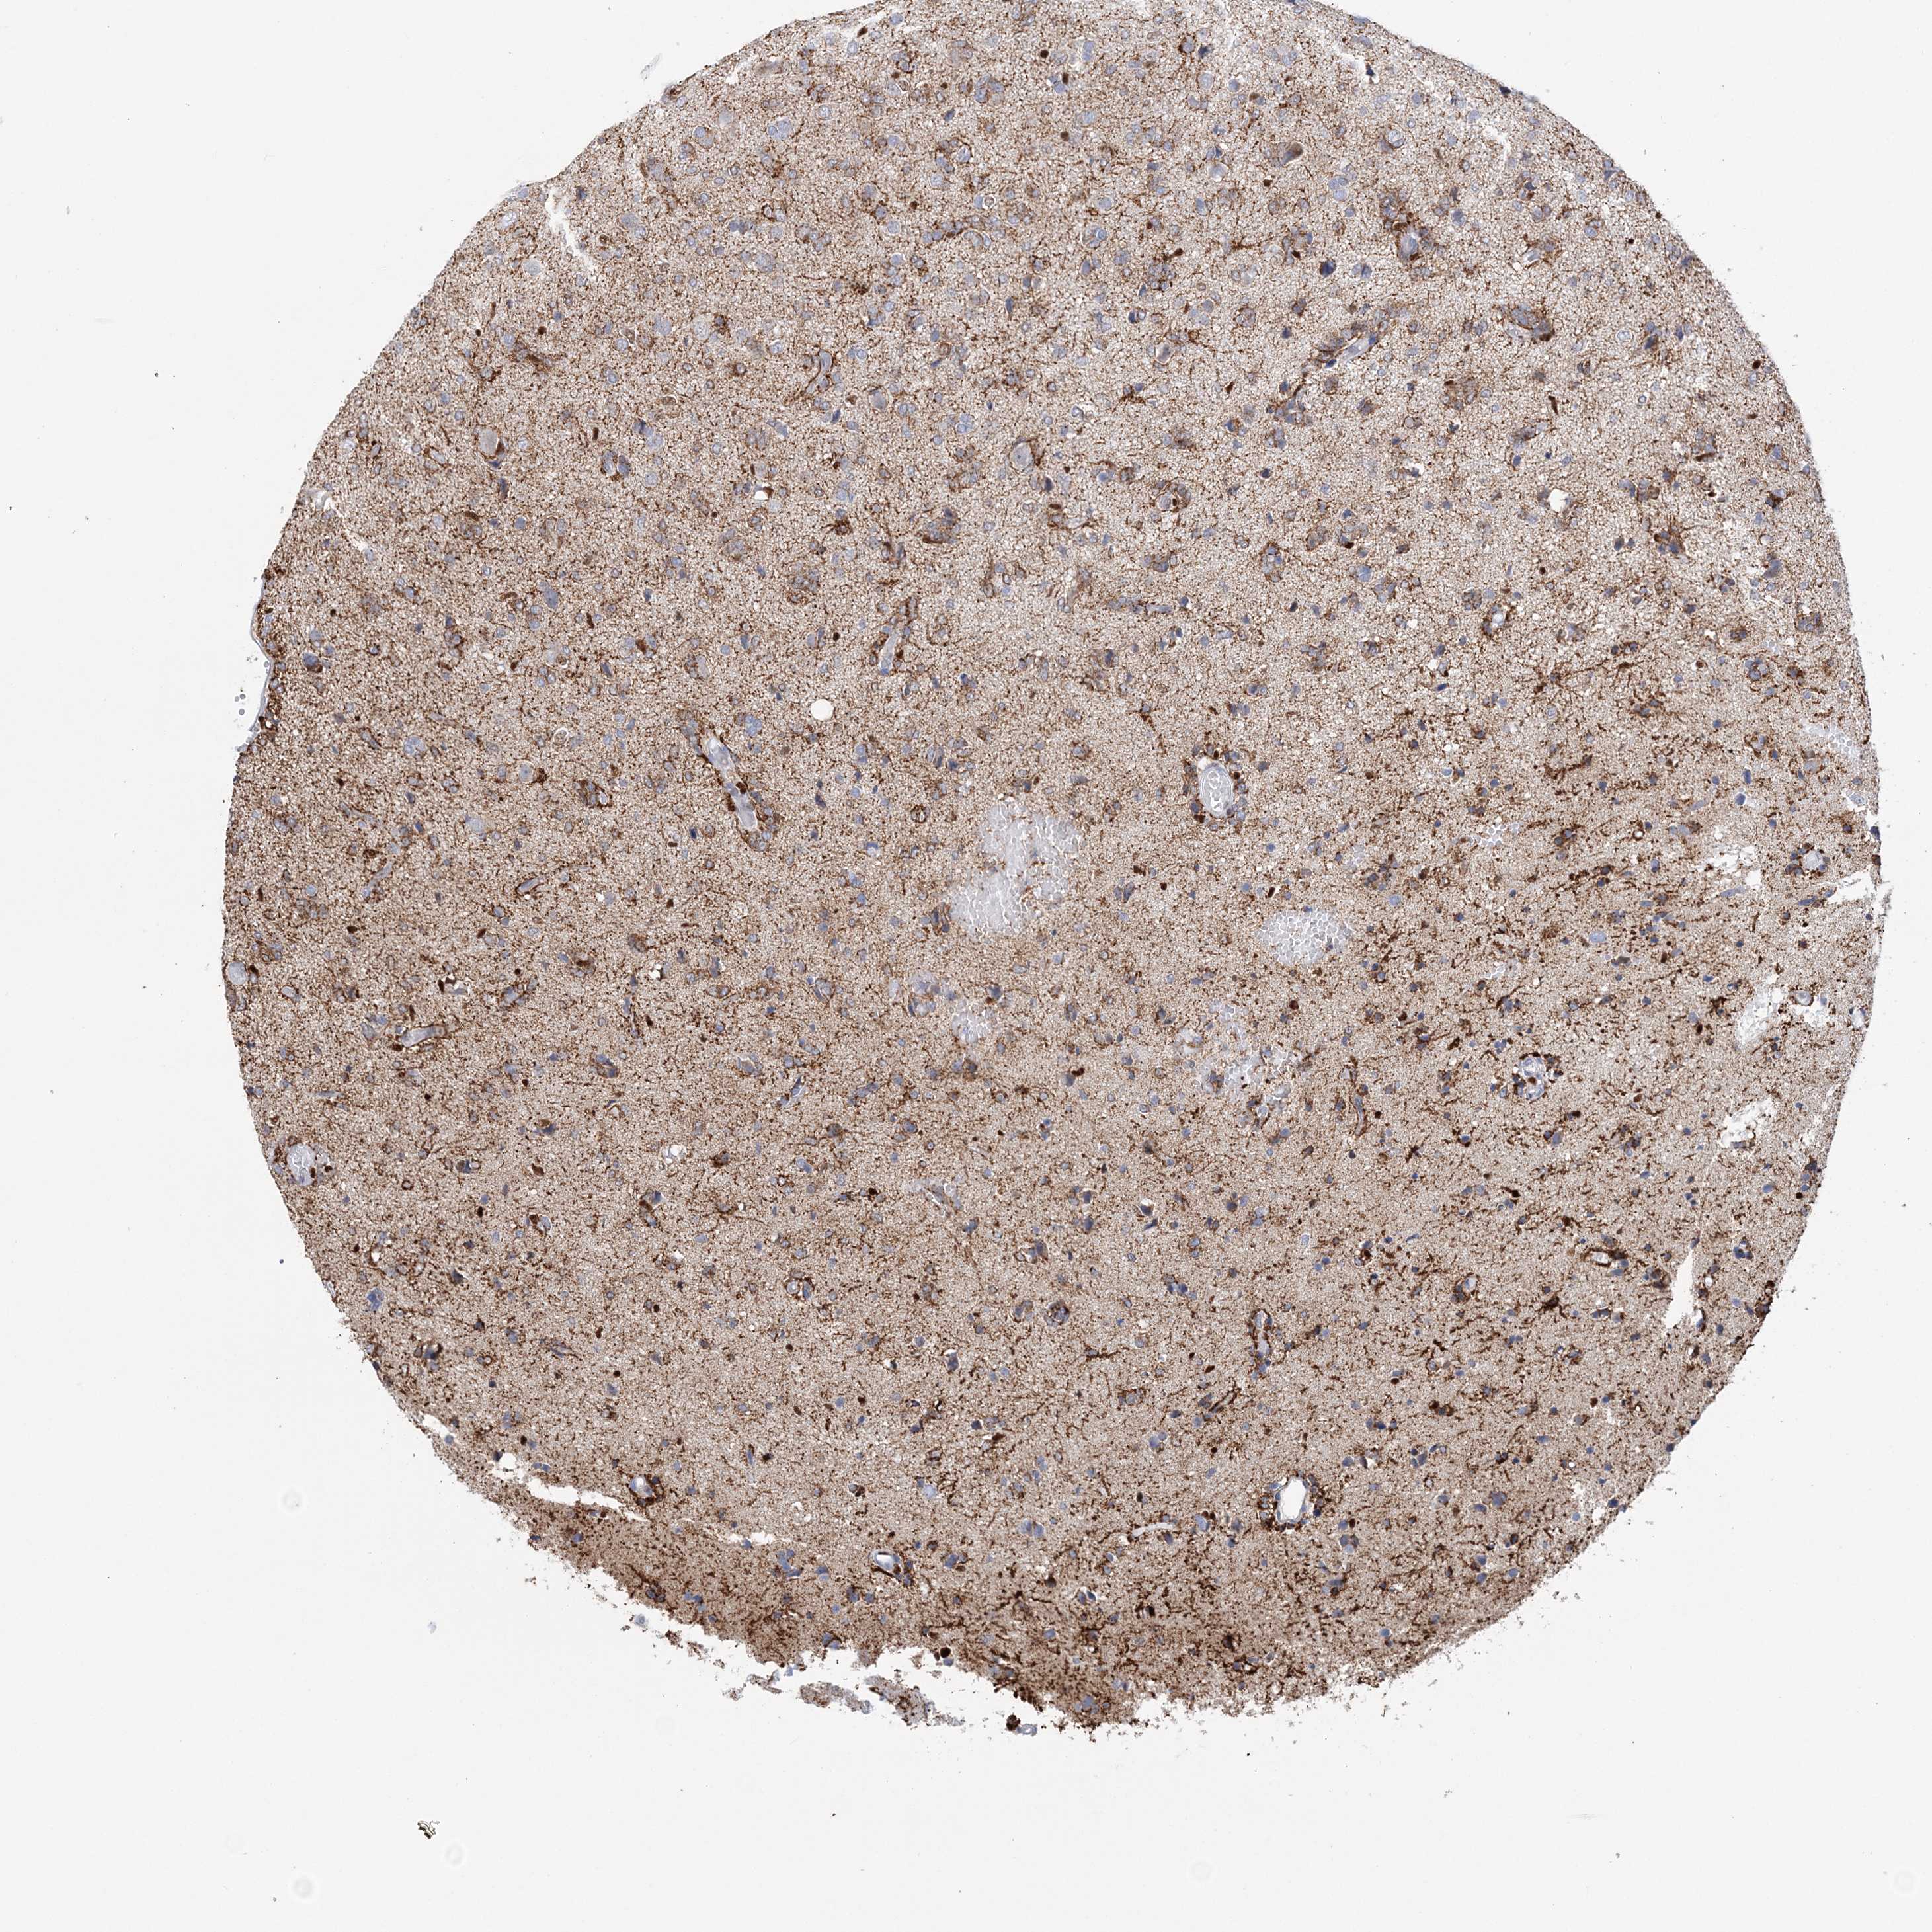

GLIOMA - Protein expressioni

A mouse-over function shows sample information and annotation data. Click on an image to view it in a full screen mode. Samples can be filtered based on level of antibody staining by selecting one or several of the following categories: high, medium, low and not detected. The assay and annotation is described here.

Note that samples used for immunohistochemistry by the Human Protein Atlas do not correspond to samples in the TCGA dataset.

Antibody stainingi

Antibody staining in the annotated cell types in the current human tissue is reported as not detected, low, medium, or high, based on conventional immunohistochemistry profiling in selected tissues. This score is based on the combination of the staining intensity and fraction of stained cells.

Each image is clickable and will lead to virtual microscopy that enables deeper exploration of all samples and also displays staining intensity scores, fraction scores and subcellular localization as well as patient and tissue information for each sample.

Antibody HPA036999

Antibody HPA041289

Staining

High

Medium

Low

Not detected

Intensity

Strong

Moderate

Weak

Negative

Quantity

>75%

75%-25%

<25%

None

Location

Nuclear

Cytoplasmic/membranous

Cytoplasmic/membranous,nuclear

Glioma, malignant, High grade

Glioma, malignant, Low grade

Glioblastoma, NOS